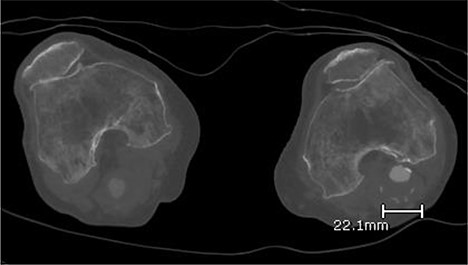

A 92-year-old female, independent from home, presented after multiple falls due to a four-month history of left foot drop. The foot drop had gradually worsened to the point that there was complete paralysis of ankle dorsiflexion and was associated with significant oedema of the foot. On examination, there was a large pulsatile mass in the popliteal fossa bilaterally. All peripheral pulses were palpable without any signs of ischemia. The most striking examination finding was complete paralysis of left ankle dorsiflexion with 0 out of 5 power. Ultrasound revealed that there were (Fig 1) bilateral popliteal artery aneurysms, which was larger on the left, causing displacement and impingement of the common peroneal nerve at the knee crease (Fig 2). Further computed tomography angiogram demonstrated an unruptured left PAA measuring 22 × 21 mm in maximal dimension over a distance of 24 mm (Fig 3). Intraluminal thrombus was also noted with 60% luminal stenosis. Distally, the arteries were heavily calcified with two-vessel runoff at the ankle. An emergency endovascular repair of the left PAA was performed by using 8 mm × 15 cm and 7 mm × 10 cm Gore Viabahn stents (Fig 4). The stents were deployed after a balloon-angioplasty and adequate decompression of the aneurysm was achieved. The postoperative period was uneventful, and patient’s pre-existing aspirin was continued. The leg and foot oedema improved rapidly over the subsequent few days. At follow-up in 12 weeks, the patient showed some return of motor function of the ankle and was walking with ankle splint. Her left leg remained well perfused with palpable pulses.

Ultrasound image of left popliteal artery aneurysm containing intramural thrombus, measuring 21 × 20 mm.